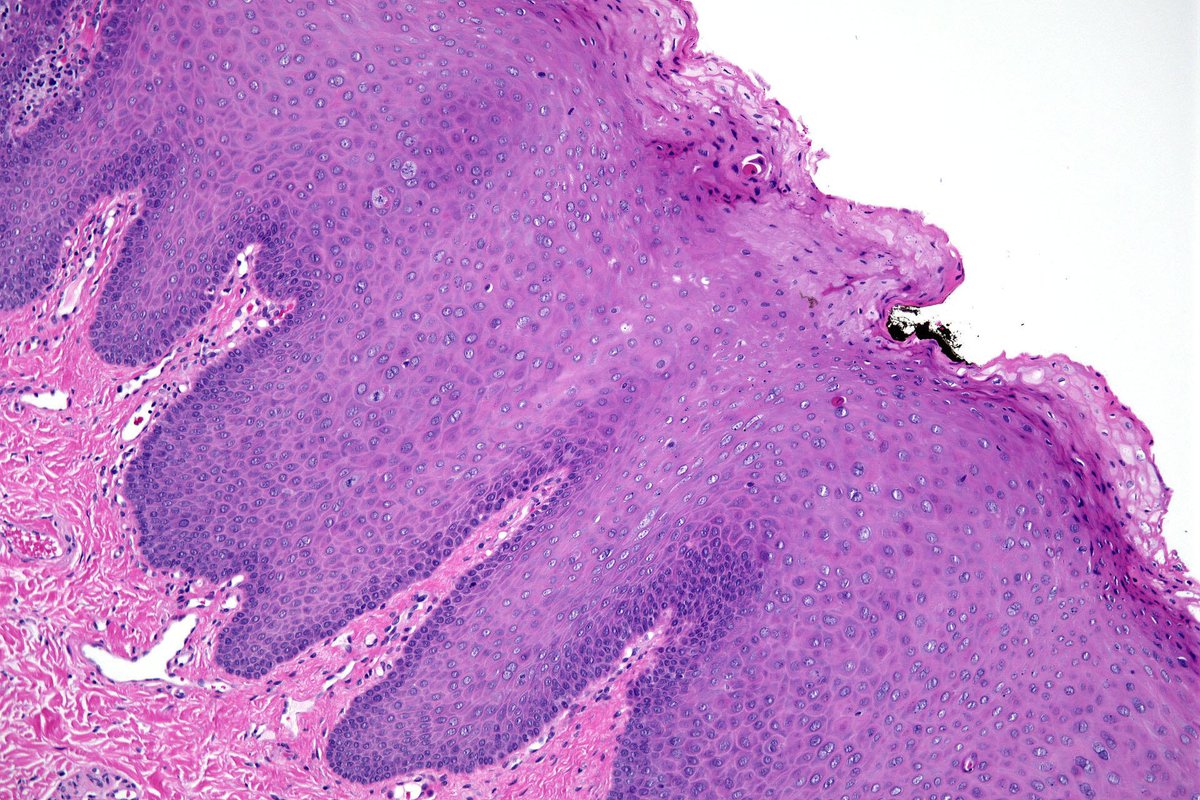

@EndoPath reports on EBV-positive neuroendocrine carcinoma of the nasopharynx, a rare cancer with distinct molecular features. Whole-exome sequencing reveals high mutational burden and key mutations in TP53, APC, and PROK2.